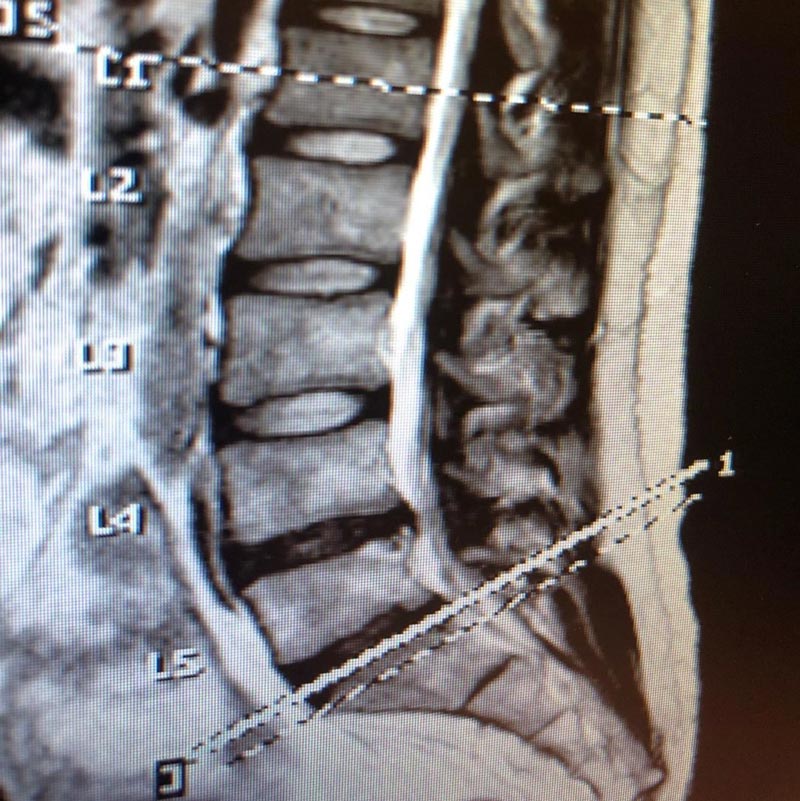

โดย พิชญ์ กาไชย ได้โพสต์ภาพฟิล์มเอกซเรย์แสดงให้เห็นหมอนกระดูกของเจ้าตัวในอินสตาแกรมส่วนตัว พร้อมข้อความว่า หมอนรองกระดูกที่มีปัญหานั้นคือข้อที่ 4 และ 5 งานนี้ทำเอาเพื่อน ๆ ดาราและแฟนคลับเข้ามาคอมเมนต์แสดงความเป็นห่วงเป็นจำนวนมาก และให้กำลังใจขอให้เจ้าตัวผ่านการผ่าตัดดังกล่าวไปได้ด้วยดี